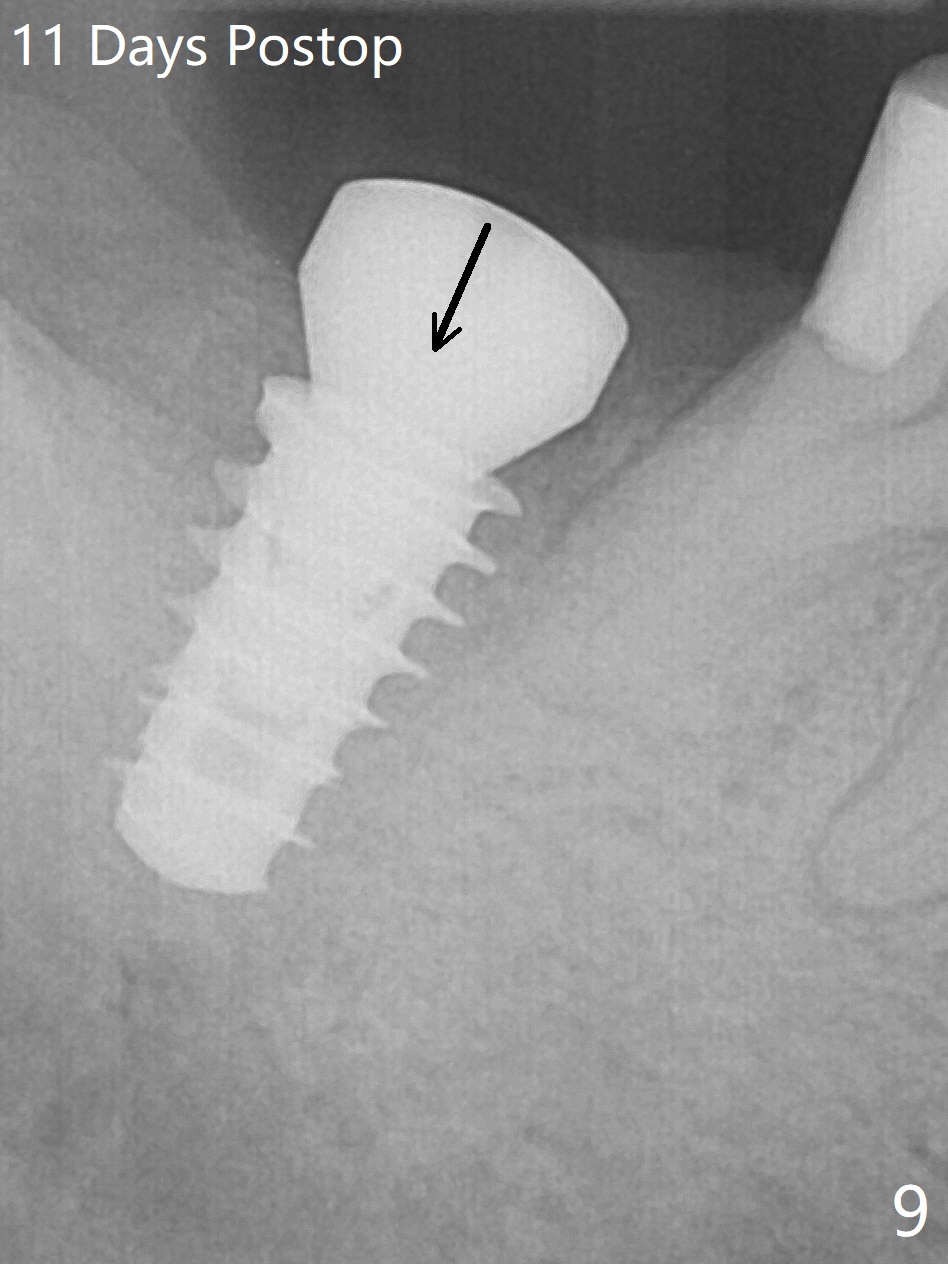

The socket shrinks with buccal plate reduction 3 months post socket preservation (Fig.5), as compared to 10 days postop (Fig.4). To restore the socket as much as possible, Magic Split is used (flapless), followed by Magic Expanders 3-3.8 mm for 11 mm (gingival level) and a 4x11mm dummy implant (Fig.6). The osteotomy is moved distal by using Lindamann bur; following 3.8 mm Magic Drill, a 4.5x11 mm dummy implant (Fig.7). Finally a definitive 5.5x9 mm implant is placed with <45 Ncm; a 6x2 mm healing abutment is placed to close the access (Fig.8). Autogenous bone harvested from the Magic Drill returns to the osteotomy mainly buccal prior to implant placement (Fig.8 *). The patient reports no discomfort immediately postop, thanks to the flapless technique. The patient has had postop pain; 11 days postop, the abutment and implant are found to be loose. After re-tightening by hand, the complex is seated deeper and more stable (Fig.9 arrow).